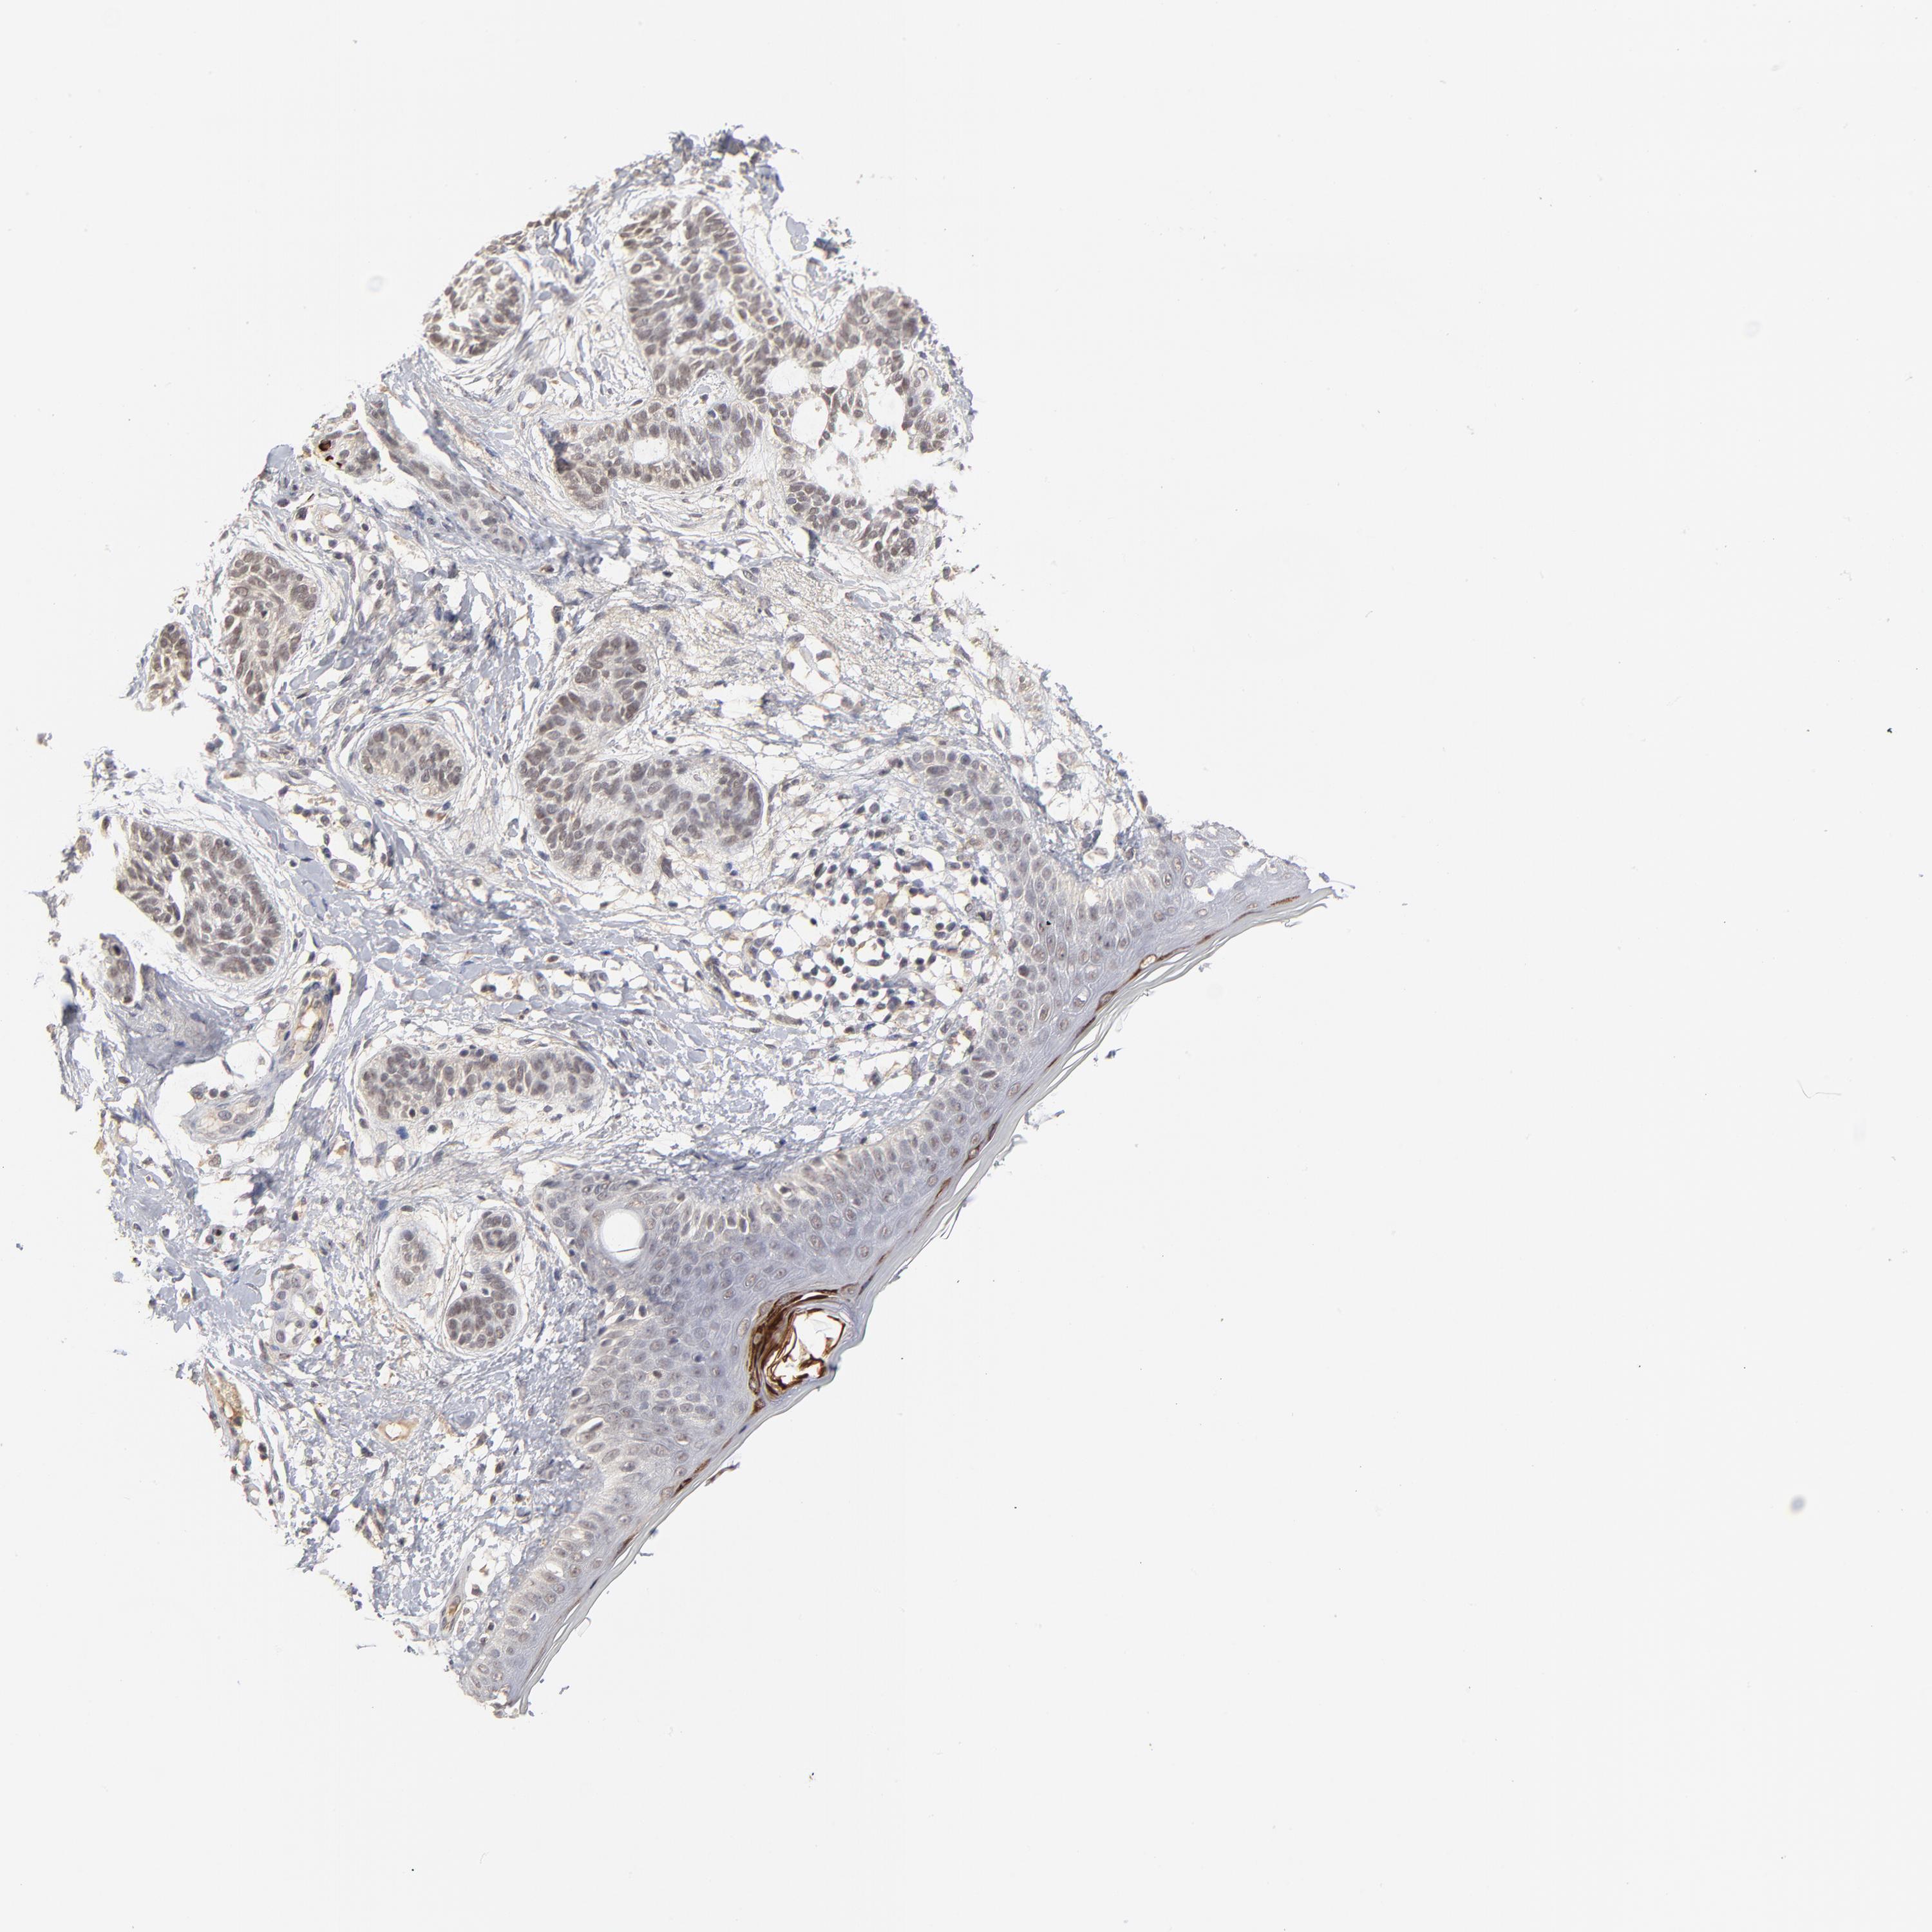

CANCER SKIN CANCER Show tissue menu

Basal cell and squamous cell cancer

SKIN CANCER - Protein expressioni

A mouse-over function shows sample information and annotation data. Click on an image to view it in a full screen mode. Samples can be filtered based on level of antibody staining by selecting one or several of the following categories: high, medium, low and not detected. The assay and annotation is described here.

Each image is clickable and will lead to virtual microscopy that enables deeper exploration of all samples and also displays staining intensity scores, fraction scores and subcellular localization as well as patient and tissue information for each sample.

Antibody HPA003293

Staining

High

Medium

Low

Not detected

Intensity

Strong

Moderate

Weak

Negative

Quantity

>75%

75%-25%

<25%

None

Location

Nuclear

Cytoplasmic/membranous

Cytoplasmic/membranous,nuclear

Squamous cell carcinoma, NOS

Basal cell carcinoma